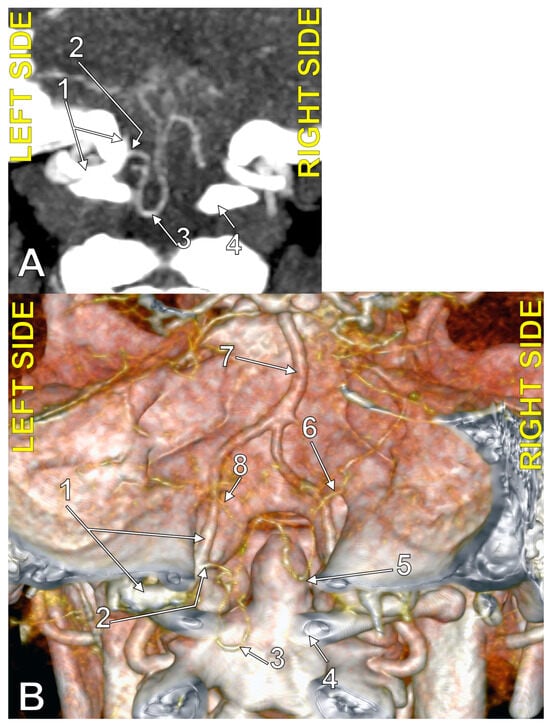

4.1. Typical PICA

4.3. Extradural Origin of the PICA

4.4. Transdural Origin of the PICA

4.8. The Caudal Loop of the PICA